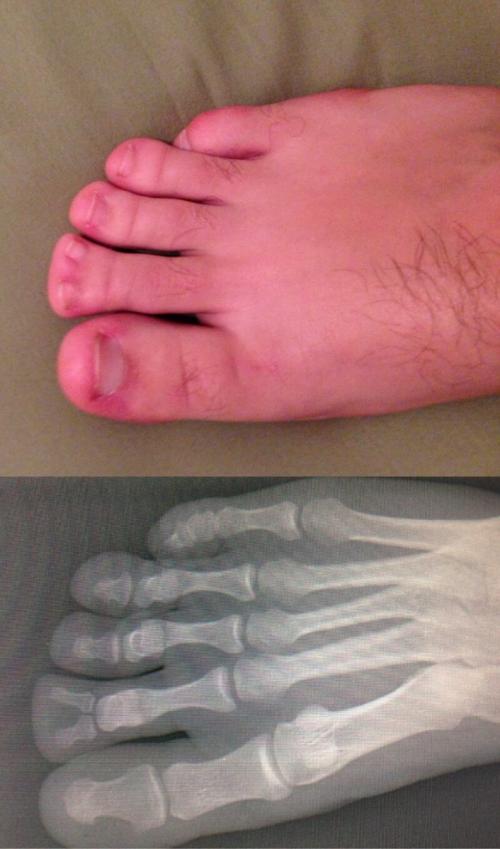

Аномальный снимок